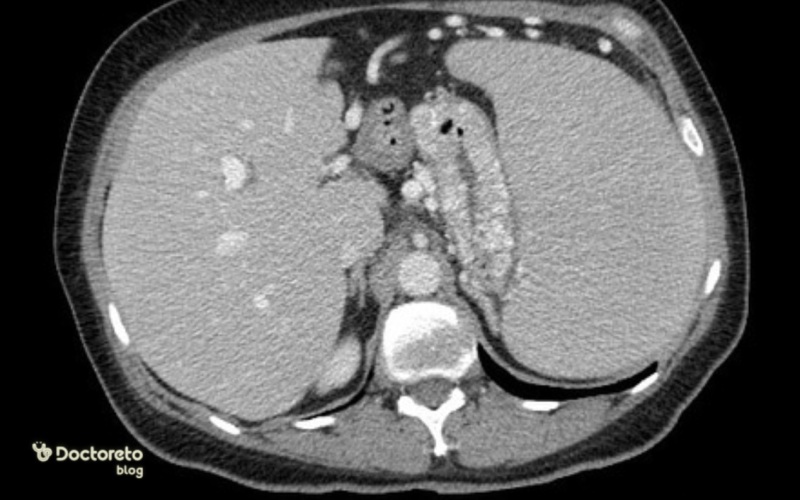

واریس معده چگونه تشخیص داده می شود؟

واریس معده معمولاً از طریق روشهای تصویربرداری و اندوسکوپی تشخیص داده میشود. اندوسکوپی فوقانی به عنوان استاندارد طلایی عمل میکند و اجازه میدهد وریدهای متسع در معده مستقیما مشاهده شوند. این روش نه تنها تشخیص را تایید میکند، بلکه خطر خونریزی را هم ارزیابی میکند.